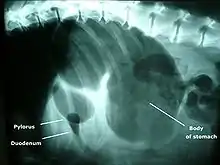

X-ray from the underside of a dog with GDV. The dark area is the buildup of gas.

Bloat in a dog, with "double-bubble" sign

A diagnosis of GDV is made by several factors. The breed and history often gives a significant suspicion of the condition, and a physical examination often reveals the telltale sign of a distended abdomen with abdominal tympany. Shock is diagnosed by the presence of pale mucous membranes with poor capillary refill, increased heart rate, and poor pulse quality. Radiographs (X-rays), usually taken after decompression of the stomach if the dog is unstable, shows a stomach distended with gas. The pylorus, which normally is ventral and to the right of the body of the stomach, is cranial to the body of the stomach and left of the midline, often separated on the X-ray by soft tissue and giving the appearance of a separate gas-filled pocket (double-bubble sign).[4]